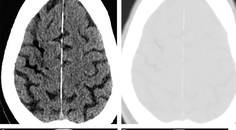

Stroke Snapshot: Reversible Cerebral Vasoconstriction Syndrome